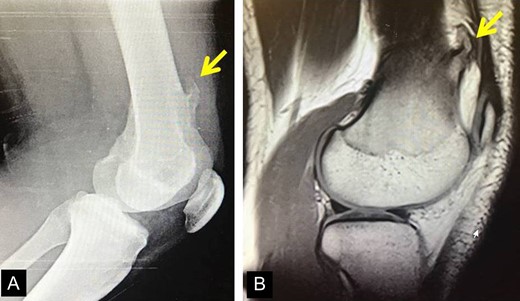

The second case involved an 18 years old male with pain and swelling at the anterior surface of the left knee, under the rectus femoris muscle over the patella. Symptoms exacerbated during knee bending over 90 degrees. X-rays and MRI revealed an extra-articular exostosis, just over the suprapatellar pouch (Figs. 3A and B). Under general anesthesia, a standard antero-lateral portal was used to access the knee arthroscopically. The capsule of the suprapatellar pouch was divided providing access to the adjacent extra-articular osteochondroma. Through a medial, a far supero-medial and supero-lateral portal, the exostosis resected by using an osteotome and removed with a grasper through the supero-lateral portal. The lesion had maximum dimensions 3.1 × 1.4 cm and its histopathological examination set the diagnosis of osteochondroma. Postoperatively, the patient was pain free with full range of knee motion. No recurrence was observed at 9 months (Fig. 4).

(A) X-ray of the exostosis in the second patient, (B) MRI depicts the lesion.